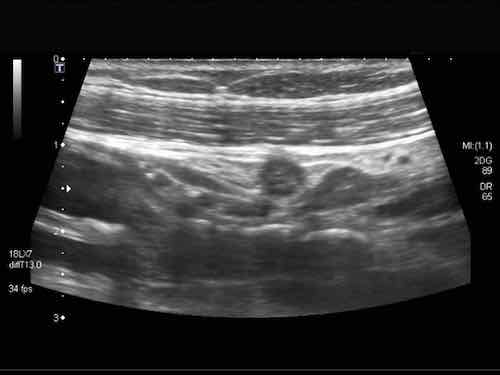

Đây là hình ảnh siêu âm của một trẻ 2 tuổi bị lồng ruột hồi manh tràng từng đợt, được khám trong khoảng thời gian giữa các cơn.

Hồi tràng với nhiều mảng Peyer sa vào manh tràng.

Hình ảnh siêu âm kinh điển của lồng ruột hồi-manh tràng ở hai trẻ khác nhau.

Trong cả hai trường hợp, đoạn hồi tràng bị lồng được định vị không đối xứng bên trong ống lồng ngoài, do mạc treo ruột tăng âm có chứa mỡ, bám vào hồi tràng và đi theo hồi tràng khi bị kéo vào trong.

Trong mạc treo, siêu âm cho thấy một hạch bạch huyết mạc treo (hbh) phóng đại ở cả hai.

Các hạch này phì đại như một phần của tình trạng tăng sản hạch bạch huyết toàn thân và khônghu trú trong lòng hồi tràng.

Do đó đây không phải là điểm dẫn đầu nguyên phát. Ở bệnh nhân bên phải, ruột thừa (mũi tên) cũng bị kéo vào trong.

Lưu ý cấu trúc đa lớp của thành bụng phía trước của phức hợp lồng ruột, đại diện cho ba lớp thành ruột bị gấp lại.